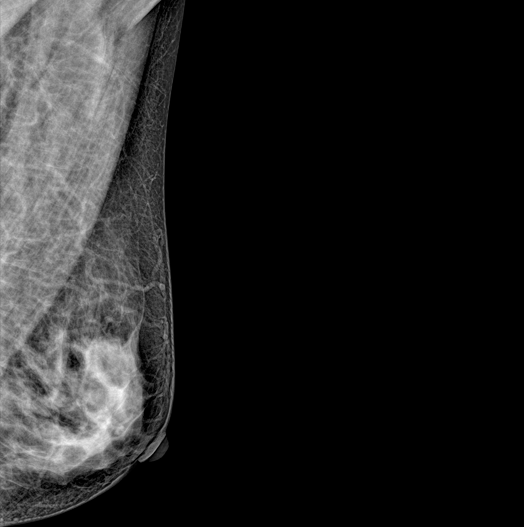

DBT (Digital Breast Tomosynthesis)

The X-ray tube moves on the breast and takes high-definition, high-resolution images with high contrast from various angles.

The images are reconstructed in 3D TO Provide accurate information about the location and condition of the lesion